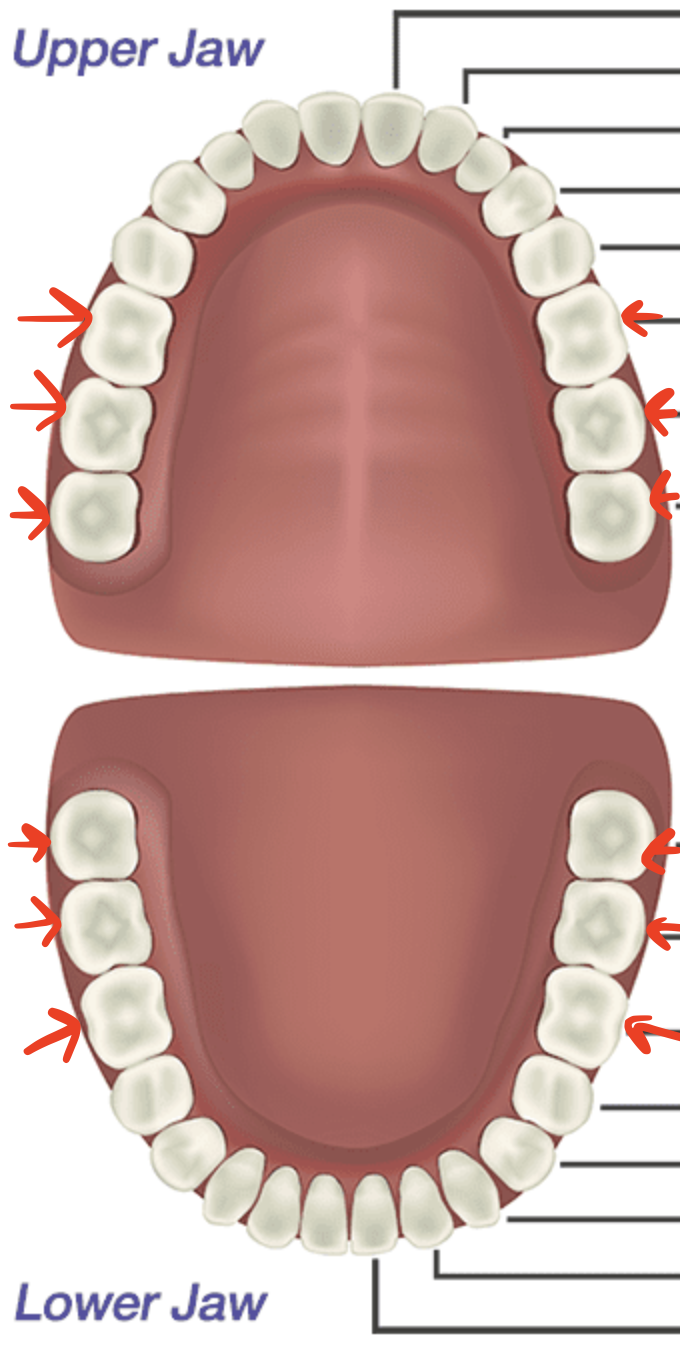

mouth

incisors

canines/cuspids

premolars/bicuspids

molars